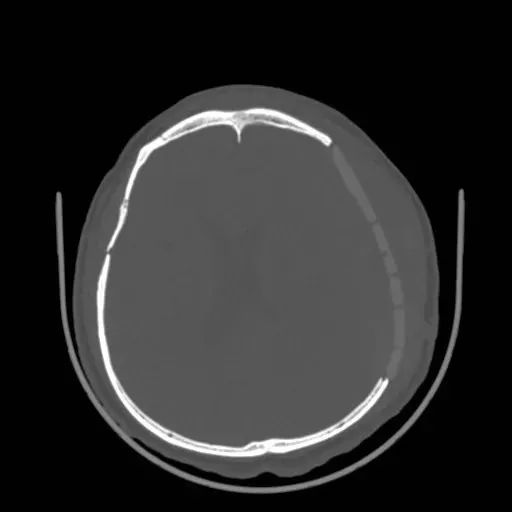

顱骨修補術后復查

張大哥在使用了邁普醫學的PEEK顱骨修補產品賽盧?做完顱骨修補術后,復查結果滿意,工作和生活也都逐漸回歸了正軌!

邁普醫學采用新型材料PEEK(聚醚醚酮)開發的賽盧?顱頜面修補系統,是基于患者CT數據個體化定制的產品,能精確復原顱頜面骨的輪廓外形,美學修復效果好。